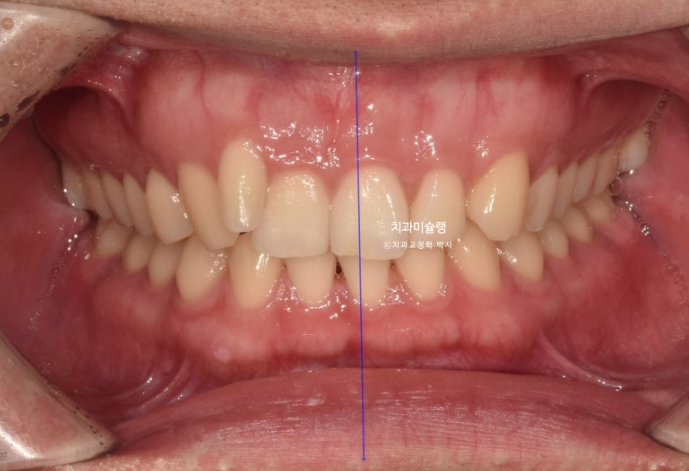

중심선은 잘 맞으며

어금니 교합도 좋습니다.

왜소치 덧니쪽으로 쏠려있던 앞니 중심선이 비로소 중간으로 맞춰졌습니다.